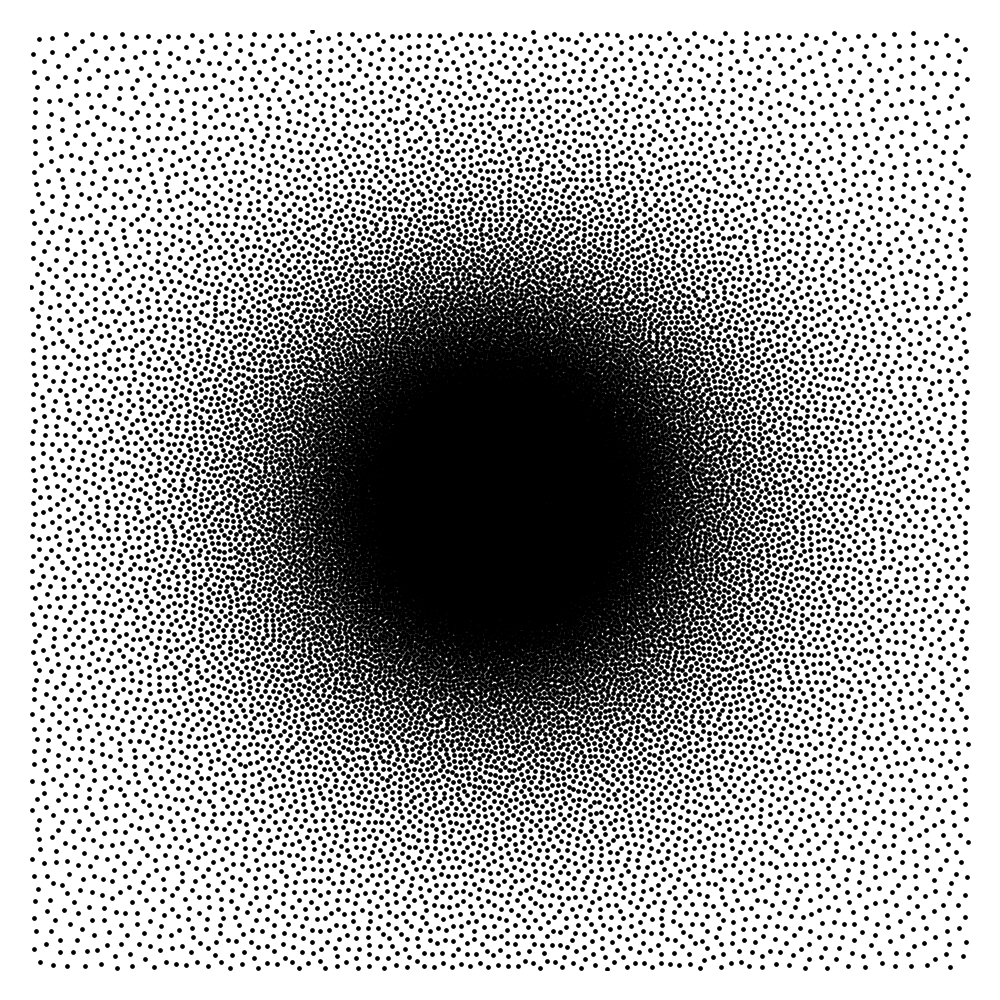

These considerations are all satisfied when using Poisson disk sampling with an adequate density Vasanawala et al. (2011) for pointwise sampling. They also led to the development of the Sparkling trajectories Chauffert et al. (2017); Lazarus et al. (2019), which incorporate additional trajectory constraints in the design.

Given the previous remarks, an important question remains open: how to choose the sampling density? An axiomatic approach leads to choosing radial densities with a plateau (constant value) at the center. The radial character ensures rotation invariance, which seems natural to image organs in arbitrary orientations. The plateau enforces Nyquist rate at the center. However, it may still be possible to improve the results for specific datasets.

A candidate space of densities

Let denote a rotation angle, denote lengths, denote a density at the center and a decay rate. For , let , . We define

| (8) |

where is a normalizing constant such that . We then smooth the function by convolving it with a Gaussian function of standard deviation :

| (9) |

The elements in this family are good candidates for sampling densities: i) they are nearly constant and approximately equal to at the center of the k-space, ii) they can be anisotropic to accommodate for specific image orientations and iii) they have various decay rates, allowing sampling the high frequencies more or less densely. Some examples of such densities are displayed in Fig. 3(a). However, the family of densities generated by this procedure is quite poor. For instance, it is impossible to sample densely both the and axes simultaneously. In order to enrich it, we propose to consider the set of convex combinations of these elementary densities. This allows us to construct more general multi-modal densities, see Fig. 3(b) for examples of such convex combinations.

Dimensionality reduction

In order to construct the family , we first draw a large family of densities . They are generated at random by uniform draws of the parameters inside a box. We then perform a principal component analysis (PCA) on this family to generate some eigen-elements . We set . Since probability densities must sum to , we orthogonalize the family with respect to the vector . Thereby, we obtain a second family that satisfies and for all . This procedure discards one dimension. The resulting PCA basis is illustrated in Fig. 3(c).

Let denote the intersection of the span of with the probability densities and the orthogonal projection on . The space of densities is the convex hull of the family projected on :

| (10) |

As illustrated in Fig. 3(b), this process overall provides a rather rich and natural family. In practice, we select a value , so that the tail of the singular values contains less than of the energy. This value is also a compromise between numerical complexity (the higher , the more complex) and the richness of the family of densities that can be generated.